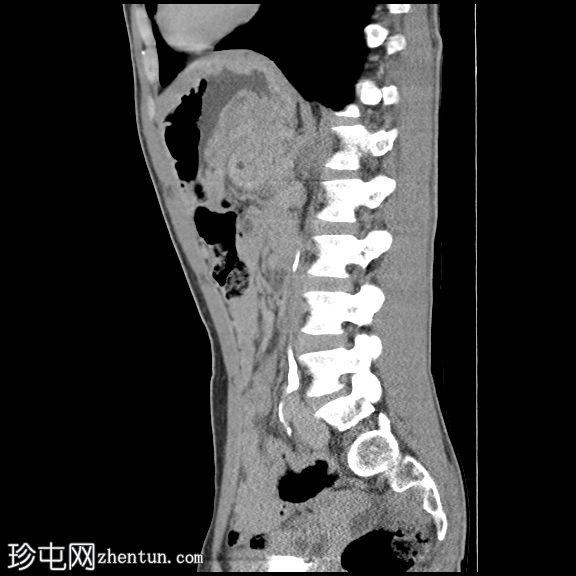

矢状位增强扫描

门静脉期

胰腺肿大。胰头、胰颈和胰体未见强化,边界不清且不规则。主胰管扩张,管内可见钙化。

胰腺实质内弥漫散在分布着大量钙化灶。

胰尾可见部分强化区域。

胰尾部钙化性假性囊肿。

影像学表现提示慢性钙化性胰腺炎伴胰尾部钙化性假性囊肿。

弥漫性实质及导管钙化是慢性钙化性胰腺炎的典型特征。

胰头及胰体无强化、形态不规则提示纤维化程度较重。

钙化性假性囊肿是一种慢性并发症,可通过囊壁钙化与肿瘤相鉴别。

CT是评估实质缺损、导管改变、钙化及假性囊肿的首选影像学检查方法。